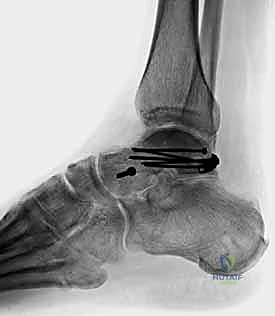

2. التصوير الإشعاعي (الأشعة السينية - X-rays)

هي الخطوة الأولى. تُطلب صور من زوايا متعددة:

* الرؤية الأمامية الخلفية (AP).

* الرؤية الجانبية (Lateral).

* رؤية الهاون (Mortise view).

* رؤية كانال (Canale View): وهي وضعية تصوير خاصة جداً لتقييم عنق الكاحل وتحديد درجة الإزاحة بدقة.

المرحلة الرابعة: التثبيت الداخلي (Internal Fixation)

بمجرد التأكد من أن العظم عاد لشكله الطبيعي تماماً، يتم استبدال الأسلاك المؤقتة بتثبيت دائم. يستخدم الدكتور هطيف أحدث الغرسات الطبية العالمية:

* مسامير التيتانيوم المجوفة (Cannulated Screws): مسامير قوية جداً يتم إدخالها عبر العظم لضغط أجزاء الكسر معاً.

* المسامير بدون رأس (Headless Compression Screws): تُستخدم في المناطق المغطاة بالغضروف، حيث تُدفن بالكامل داخل العظم لكي لا تحتك بالمفصل وتسبب تآكلاً.

* الشرائح المعدنية الدقيقة (Mini-Plates): تُستخدم أحياناً لتدعيم التثبيت في حالات التفتت الشديد (Comminution) حيث لا تكفي المسامير وحدها.

يتم وضع المسامير عادة من اتجاهين (من الأمام للخلف، ومن الخلف للأمام) لإنشاء هيكل ميكانيكي صلب يتحمل الضغوط.